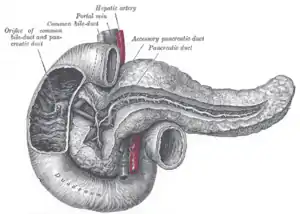

The pancreatic duct.

The pancreatic duct. Carcinoma of Ampulla